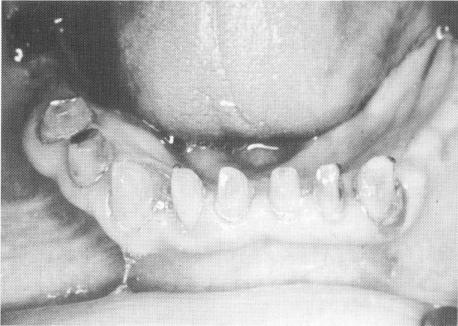

The remaining mandibular teeth were prepared for full crown restorations, and blade implants were placed in both posterior edentulous areas (Fig. 15-105) . A full arch fixed prosthesis was fabricated and cemented over the implants and teeth (Fig. 15-106) .

Fig. 15-105. The mandibular teeth were prepared, and a blade implant was placed posteriorly on each side of the mandible.